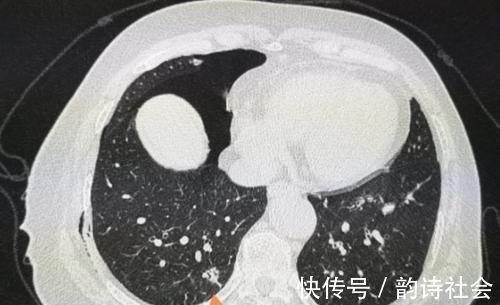

我们观察她的CT片,在她的右肺下叶有一个肺大泡(黄色箭头),紧挨着胸膜,由于气流冲击被顶破了,肺里的气体进入胸腔发生气胸。

这种少量气胸并不严重,保守观察就好,会慢慢吸收。

但我们同时又有一个意外的发现:橙色箭头是一个肺结节,

文章插图

结节外侧有胸膜牵拉,内部可以看到支气管充气征,综合分析符合一个高分化腺癌的CT表现。

这个小肿瘤没有症状,可以通过胸腔镜微创切除,手术后5年生存率接近100%。

但如果没有这个气胸发作,拖个一年半载的,等出现肺部症状再来,就不好说了。